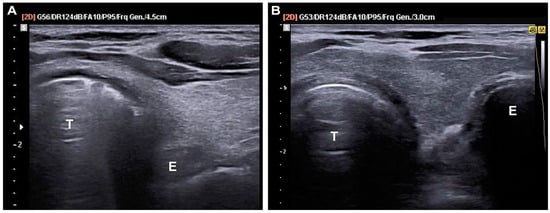

2.3.4. Data Collection